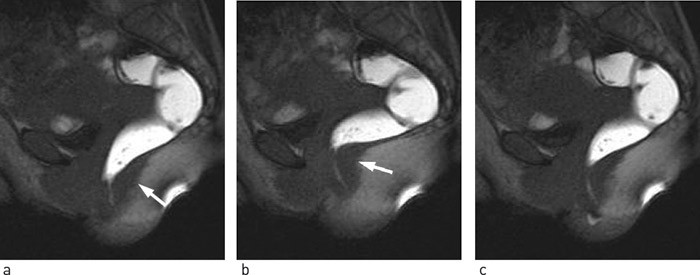

Overaktiv bekkenbunnssyndrom er en eksklusjonsdiagnose, og det finnes ingen gullstandard for diagnostisering. Klinisk vil det støtte diagnosen dersom smertene reproduseres ved digital palpasjon av bekkenbunnen og m. puborectalis (ramme 2). Injeksjon av lokalbedøvelse i m. puborectalis vil medføre smertefrihet, og kan brukes som hjelpemiddel for å vise hvor smerten kommer fra. En velegnet objektiv undersøkelse for å dokumentere overaktivitet i bekkenbunnsmuskulaturen er røntgen defekografi (3). Dette er en dynamisk undersøkelse der pasienten får et røntgentett klyster som skal kvitteres under gjennomlysning sittende på dostol. Testen bidrar følgelig med informasjon om strukturelle abnormaliteter i tillegg til funksjonelle parametre som: anorektal vinkel i hvile og under defekasjonsforsøk, diameter av analkanalen, og grad av rektal tømming. Røntgendefekografi av pasienter med syndromet vil vise overaktiv bekkenbunnsmuskulatur og eventuelt paradoks bevegelse under defekasjon, med opphevet evne til åpning av den anorektale vinkelen (8, 30) (fig 4). Nyere studier viser til MR-defekografi som en enda bedre egnet undersøkelsesmetode for å påvise patologiske forhold i bekkenbunnen, deriblant overaktiv bekkenbunn-syndrom (3, 30). Typisk klinisk bilde samt sikker eksklusjon av andre mulige årsaker kan gi diagnosen på tross av negative funn ved defekografi. Videre vil positive defekografifunn ikke være ensbetydende med diagnosen. Sensitivitet og spesifisitet for undersøkelsen er ikke tallfestet.